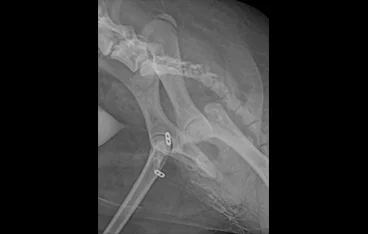

고관절 질환

THR, FHNO, Toggle pin

• FHNO

• FHNO 수술 전

FHNO 수술 후

• THR

• THR 전

THR 후

• toggle pin

• toggle pin 전

toggle pin 후